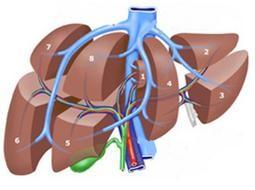

Figuur 2: Acht leversegmenten volgens Couinaud